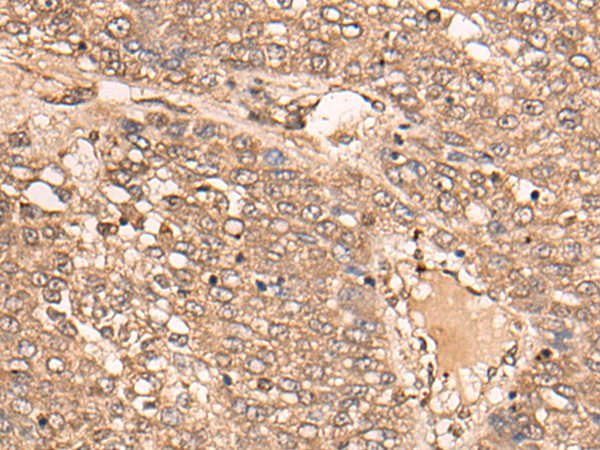

IHC positive control: |

Human liver cancer |